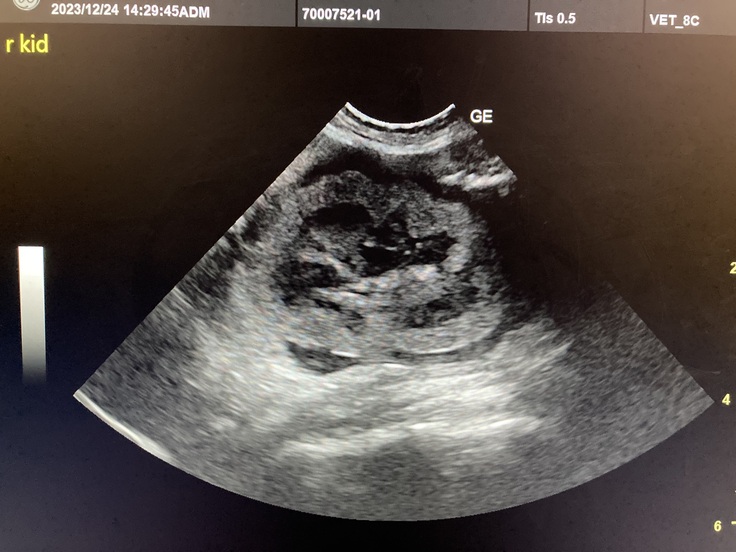

病院に到着して問診と診察を受け、食欲不振の原因が分からないので血液検査とエコー検査をしてもらい、原因が判明しました。

血液検査の結果で腎臓の数値が上がっていて、炎症もしているとの事でした。

左右両方の腎臓のエコー写真も見せて頂きました。

この影響で食欲不振になっていると担当獣医師が教えてくれました。